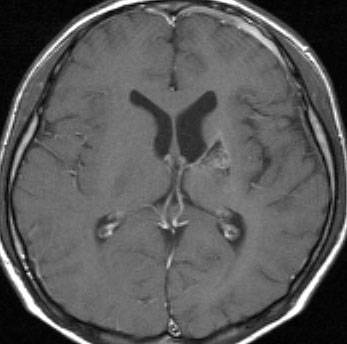

10歳くらいから身長の伸びが遅くなって,12歳で食欲低下と体重減少がありました。左のMRIはガドリニウム造影MRIで,視床下部と下垂体を侵す神経下垂体ジャーミノーマです。CTでは小さな石灰化(白い点)がみえます。CT検査は不必要なものでした。

germinomaの視床浸潤:ミッキーマウスの耳

松果体ジャーミノーマは両側視床に浸潤して視床浮腫を生じます。真ん中に第3脳室後半部の割れ目が残っているのが特徴的な所見です。ミッキーマウスの耳みたいになります。かなり特異的な所見であり診断に有用です。右下は治療後です。